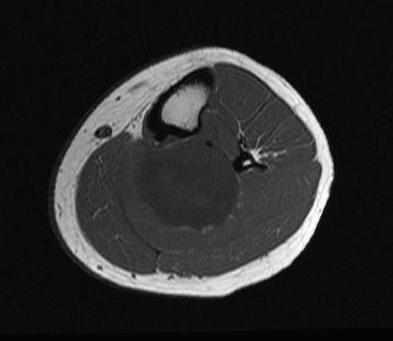

Plexifom

- bag of worms feeling

- usually develop from major nerves

- potential to become malignant